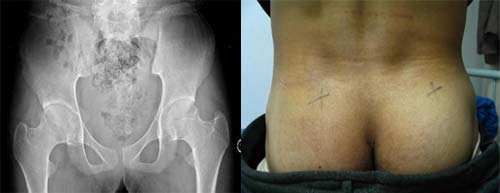

(图:小李入院时检查所拍摄的ct及症状)

CT检查:双髋关节毛糙,双骶骼关节部分融合,关节间隙狭窄,部分关节可见锯齿状,左侧股骨头结构模糊不清。